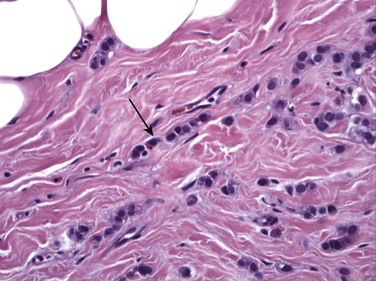

ILC is very different from IDC. On histologic examination, it is characterized by a lack of e-cadherin. Why are we boring you with pathology? Although the study of Latin among premedical students is less common these days, e-cadherin sounds rather like “adhere,” which explains ILC in a nutshell. The cells in ILC lose their ability to adhere to one another, resulting in cancers that are very infiltrative in the breast, like a spider web. ILC is characterized by lines and sheets of cells invading into the breast tissue (Fig. 11-1). This insidious growth pattern and failure to elicit a desmosplastic reaction can make ILC difficult to detect on clinical examination and mammography.

FIGURE 11-1 Histology of ILC.

ILC is characterized by single file sheets of cells (arrow). Note that there is little lymphocytic response or edema. (Reprinted with permission from Harvey JA. Unusual breast cancers: Useful clues to expanding the differential diagnosis. Radiology 2007;242:683-694.)